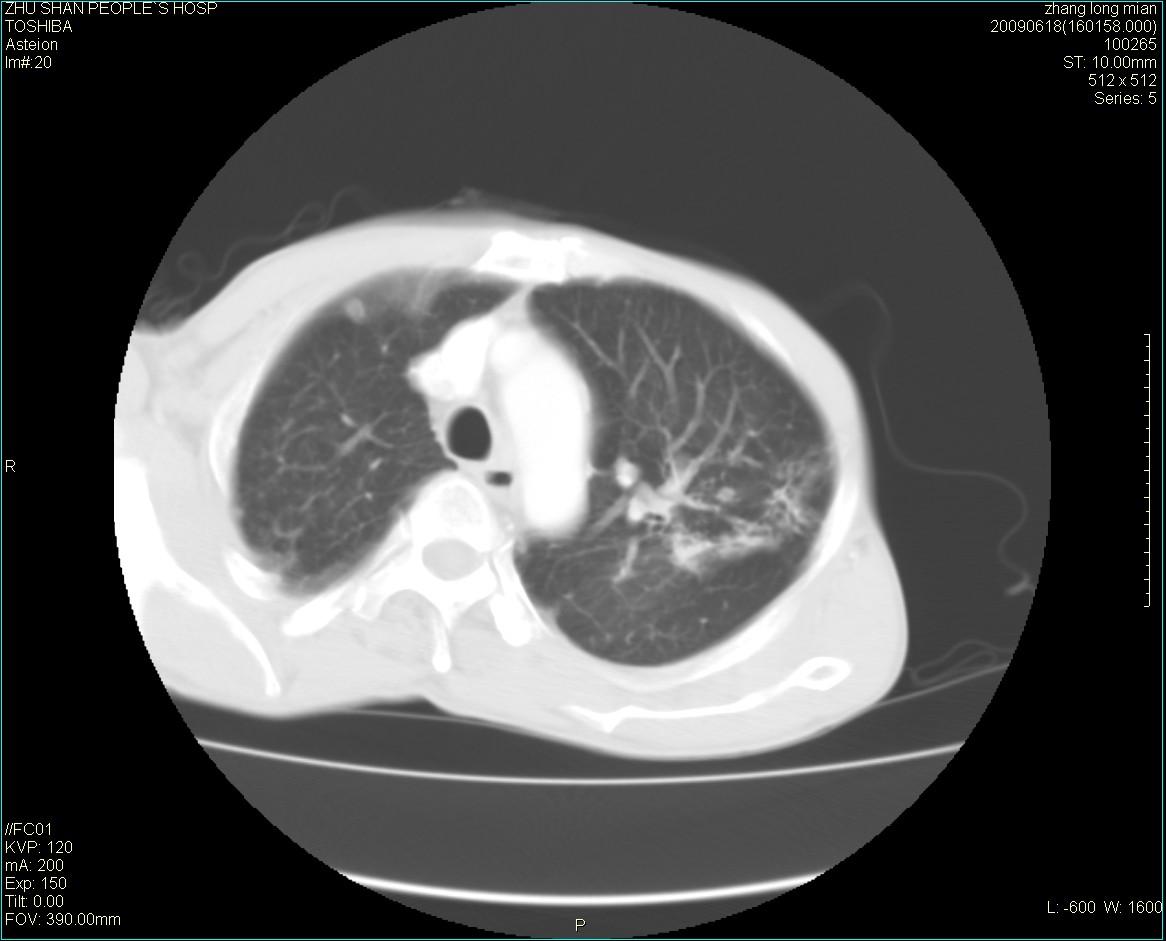

男性 65岁 胸片发现右下肺包块.诊断肺ca并纵隔转移没有问题吧!

两侧胸廓不对称,右侧呈塌陷改变,右肺萎缩。

右下肺见浅分叶状软组织块影,边缘有毛刺,其下部似见不完整偏心空洞影,邻近胸膜凹陷征,并胸腔积液。

增强见纵隔区气管隆突上下及左肺门区肿大淋巴结。左肺感染性病灶。

另见右上肺见一枚小结节影,性质待定。